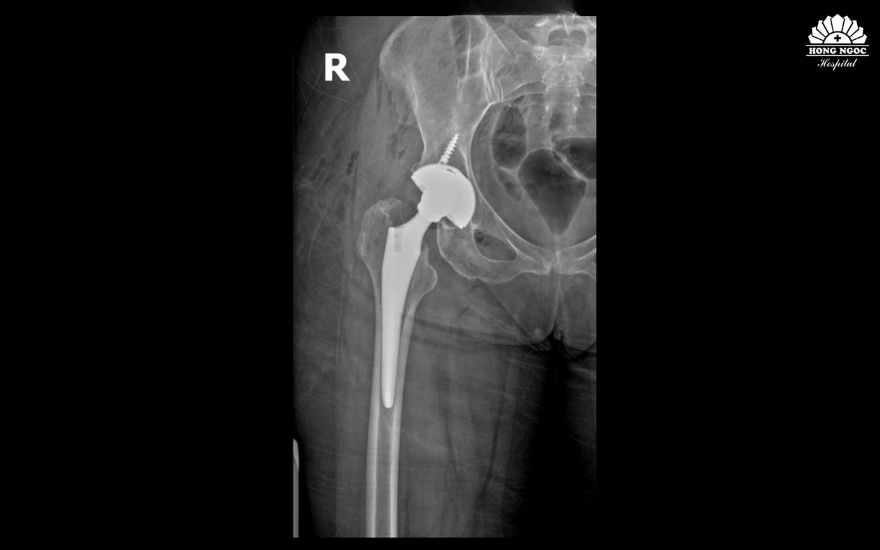

Phim chụp khớp háng của bệnh nhân Ronit sau phẫu thuật.

Tại BVĐK Hồng Ngọc - Phúc Trường Minh, bà Ronit được TS.BS Lê Quang Huy - Trưởng khoa Ngoại Chấn thương chỉnh hình - Thần kinh sọ não trực tiếp thăm khám. Sau khi đánh giá toàn diện các triệu chứng kết hợp cùng kết quả trên phim chụp X-quang, bác sĩ xác định bà bị gãy kín cổ xương đùi phải và cần phẫu thuật thay khớp háng toàn phần không xi măng sử dụng loại khớp hai chuyển động để giảm đau, khôi phục cấu trúc và chức năng vận động.

Sau hơn 1 giờ, ca phẫu thuật diễn ra thành công, phần cổ xương đùi bị gãy được thay thế bằng khớp nhân tạo có độ bền cao, chịu lực tốt, phù hợp cho bệnh nhân duy trì vận động lâu dài.